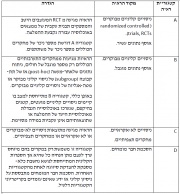

| 16:37, 7 במרץ 2015 | Gold table3.jpg (קובץ) |  |

233 קילו־בייטים | Motyk | 1 | |

| 16:35, 7 במרץ 2015 | Gold table2.jpg (קובץ) |  |

210 קילו־בייטים | Motyk | 1 | |